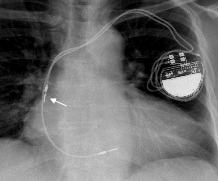

四、影像确认

X 光:脱位、穿孔、电极破裂、连接不良等;

心脏超声:穿孔,心包积液等;

为什么双极不起博起搏器故障怎么办?简单 5 步轻松搞定 | 上海心律失常论坛_https://www.jmylbn.com_新闻资讯_第13张

为什么双极不起博起搏器故障怎么办?简单 5 步轻松搞定 | 上海心律失常论坛_https://www.jmylbn.com_新闻资讯_第14张

图片来源:课件 PPT